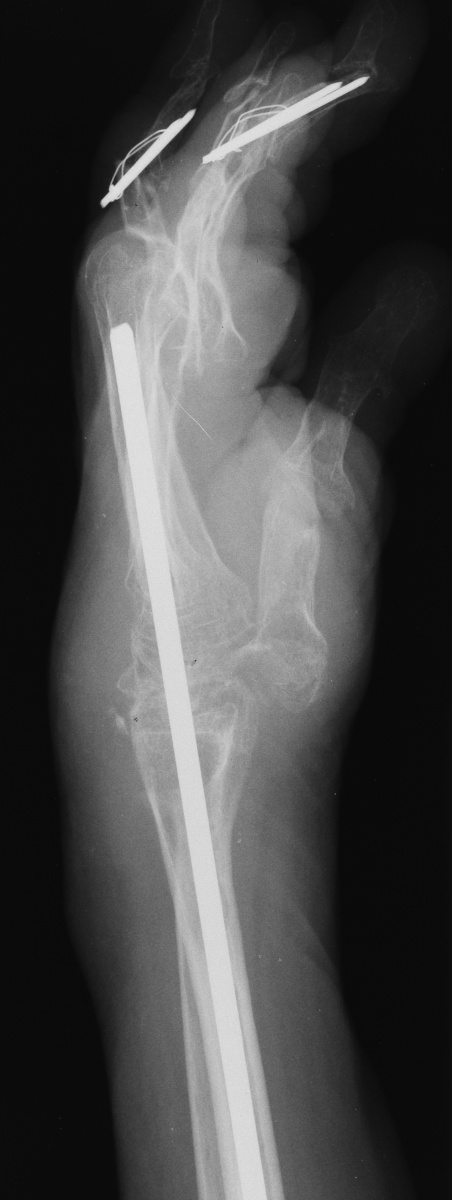

Xrays show radiocarpal collapse, proximal migration of the proximal phalanges, flail PIP joints and loss of the proximal half of the dorsal cortex of the proximal phalanges.

This woman has undergone multiple rheumatoid procedures elsewhere. On the right, these included right wrist fusion and MCP silicone arthroplasties. On the left, silicone arthroplaties of the thumb MCP, index and middle PIP joints and arthrodesis of the thumb IP, ring and small PIP koints. She wanted improvement of her left hand function, which was hindered by wrist pain and flail fingers.

Her left index and middle fingers are grossly unstable.